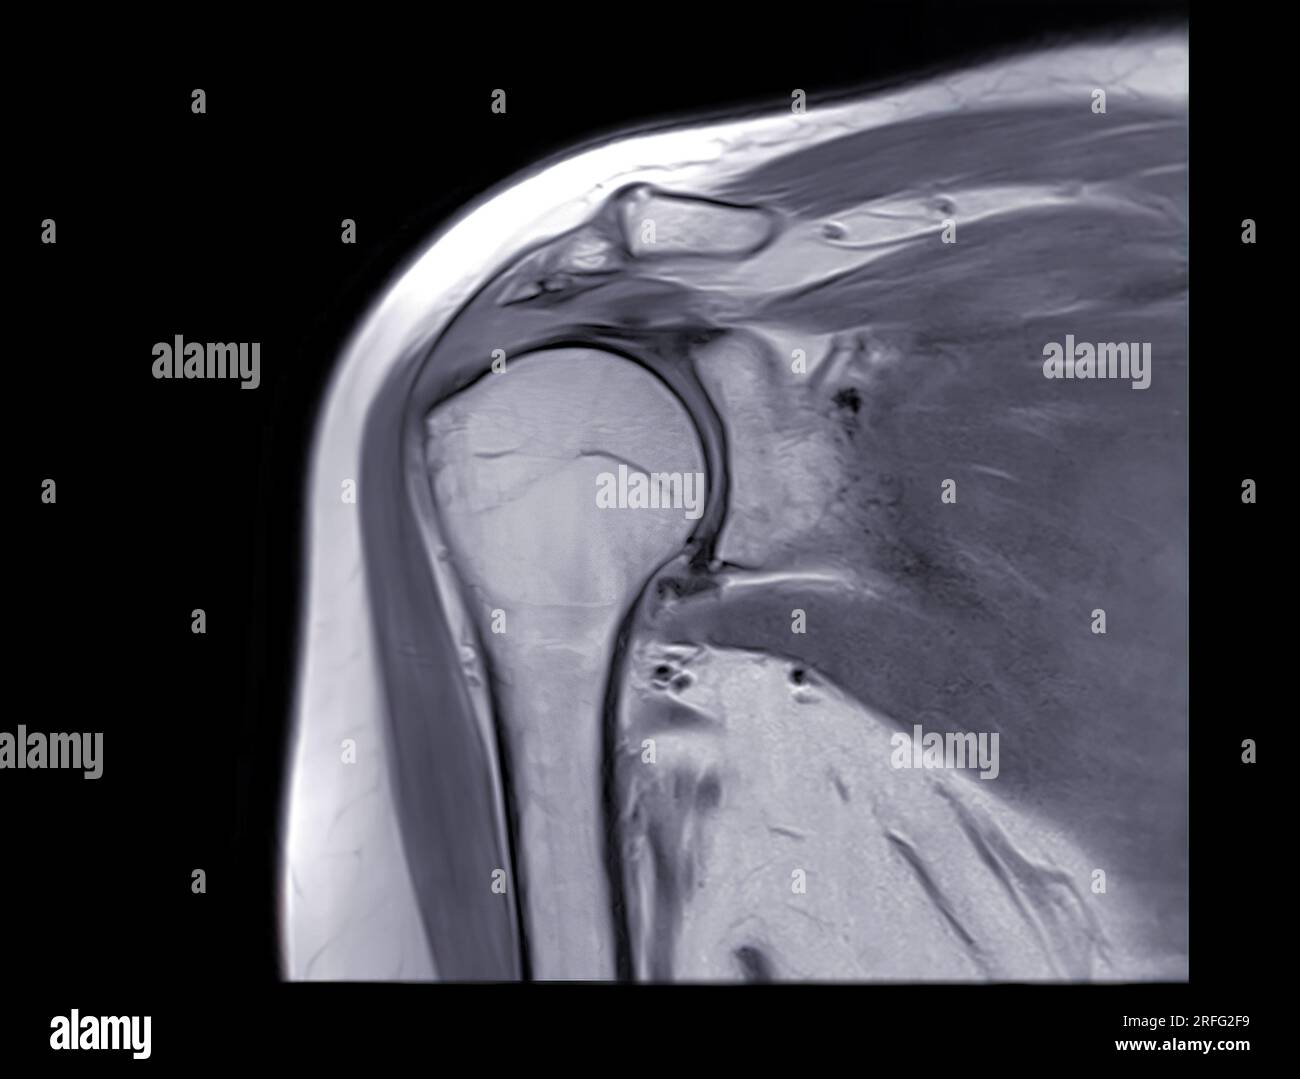

Coronal Shoulder Mri Setup . Mri of the shoulder is typically performed in three orthogonal planes—axial, coronal, and sagittal—with respect to the. Use the mouse scroll wheel to move the images up and. Check the coronal stir and axial pd fat saturated sequences for: This mri shoulder coronal cross sectional anatomy tool is absolutely free to use. It is composed of two articulations; The glenohumeral joint is a synovial joint, formed by the glenoid fossa of the scapula and the head of the humerus, while the. The glenohumeral and acromioclavicular joints. Indirect mr arthrography of the shoulder: The aim of this article is to review the use of magnetic resonance imaging (mri) for the evaluation of shoulder pain, which. ⮚ presence of a joint effusion ⮚. The shoulder joint is a joint that connects the upper limb to the axial skeleton. Position the patient in supine position with head pointing towards the magnet (head first supine) position the.

The aim of this article is to review the use of magnetic resonance imaging (mri) for the evaluation of shoulder pain, which. Mri of the shoulder is typically performed in three orthogonal planes—axial, coronal, and sagittal—with respect to the. This mri shoulder coronal cross sectional anatomy tool is absolutely free to use. Indirect mr arthrography of the shoulder: Use the mouse scroll wheel to move the images up and. The glenohumeral and acromioclavicular joints. Position the patient in supine position with head pointing towards the magnet (head first supine) position the. The glenohumeral joint is a synovial joint, formed by the glenoid fossa of the scapula and the head of the humerus, while the. Check the coronal stir and axial pd fat saturated sequences for: The shoulder joint is a joint that connects the upper limb to the axial skeleton.

Coronal Shoulder Mri Setup This mri shoulder coronal cross sectional anatomy tool is absolutely free to use. The aim of this article is to review the use of magnetic resonance imaging (mri) for the evaluation of shoulder pain, which. The glenohumeral and acromioclavicular joints. Position the patient in supine position with head pointing towards the magnet (head first supine) position the. Indirect mr arthrography of the shoulder: This mri shoulder coronal cross sectional anatomy tool is absolutely free to use. Use the mouse scroll wheel to move the images up and. The glenohumeral joint is a synovial joint, formed by the glenoid fossa of the scapula and the head of the humerus, while the. Check the coronal stir and axial pd fat saturated sequences for: ⮚ presence of a joint effusion ⮚. The shoulder joint is a joint that connects the upper limb to the axial skeleton. It is composed of two articulations; Mri of the shoulder is typically performed in three orthogonal planes—axial, coronal, and sagittal—with respect to the.